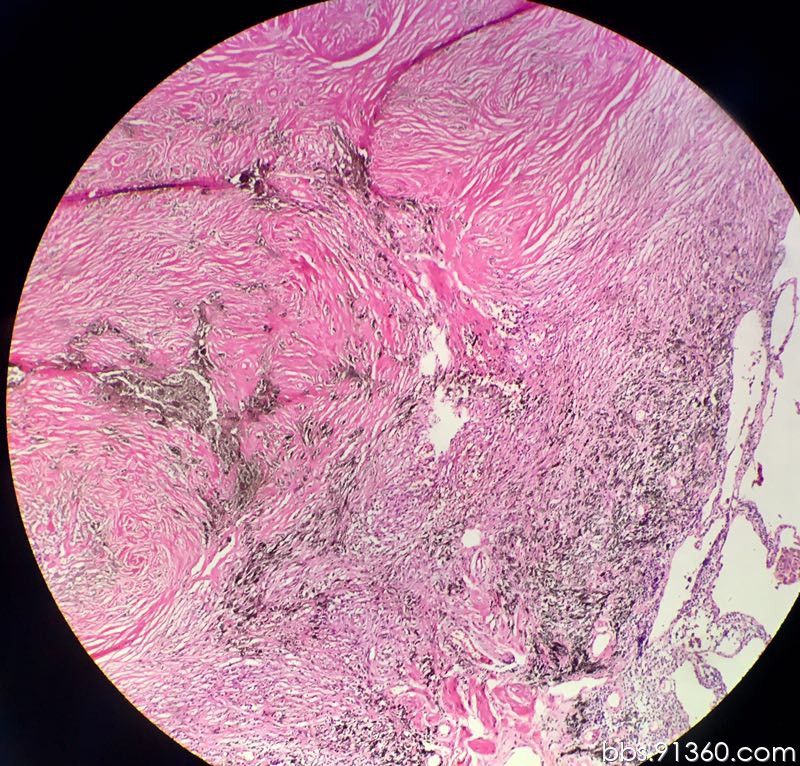

肺纤维化切片

左肺下叶 伴有陈旧性坏死的纤维化结节讨论病例【胸部等器官疾病诊断

肺组织慢性炎伴间质纤维化病例【胸部等器官疾病诊断论坛病例123】